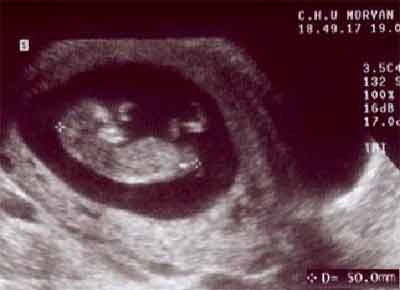

Embryon en flexion